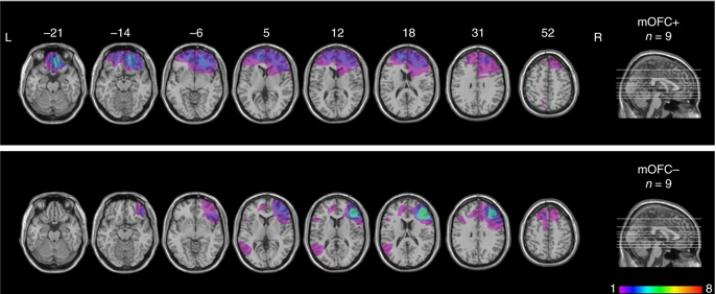

但是只有气味不用绕路,通过鼻子漂浮到大脑的嗅球中,直接绕过丘脑,通过「一两个突触」,用最短路线到达了杏仁核和海马体。

图片来源:《Nature Communications》

而杏仁核是处理情绪的区域,海马体则是进行学习和记忆的区域。

于是,一旦闻到熟悉的味道,大脑的海马体便会被瞬间激活,杏仁核的情感唤起也由此展开。

杏仁核和海马体是情感与记忆的中枢,这就导致了情感、记忆和气味之间的密切联系。

在《Nature Communications》杂志发表的一项研究证实,人类的嗅觉可能与空间记忆力存在关联,且受到同一个脑区的控制。